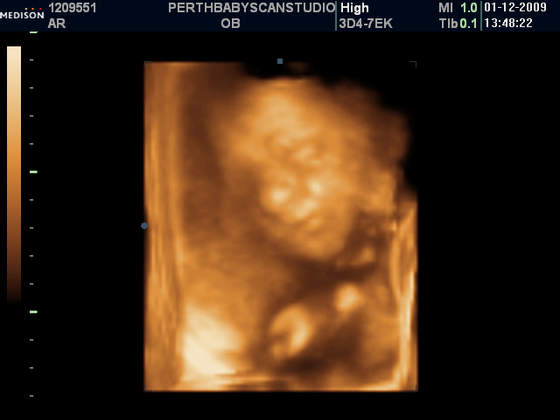

W naszym miescie na polnocy szkocji, o ile nie ma zadnych komplikacji, robia programowo tylko jedno usg (w 13 tygodniu):-(. My bardzo chcielismy znac plec dziecka dlatego pojechalismy do innego miasta (2 godziny drogi) i zaplacilismy £75 za usg ktore mialo byc w 2d ale mila pani doktor zrobila nam prezent na swieta i dostalismy tez zdjatka w 3d (ktore normalnie kosztuja £130) . Teraz przynajmniej wiemy ze bedziemy mieli sliczna i zdrowa coreczke:-) A to nasza Maja

Taka Misia - Pysia Moja:-)